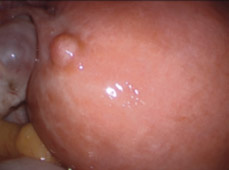

Myom : Ankara Myom Tedavisi Prof Dr Tayfun Gungor : Myom nedir, bulunduğu yere göre şikayetleri nelerdir?. Myom ameliyatı sonrasında nasıl gebe kaldım,süreç nasıl ilerledi,şu an ki myom ve kistlerimin boyutu nedir ve gebelik. Myomların kesin nedeni bilinmemekle beraber östrojenin (kadınlık. Miyom düz kas ve bağ dokusundan oluşur. Myom nedir (miyom nedir ?) (kadın rahminde miyom nedir ). Rahim yumruları (myomlar) rahimdeki selim (iyi huylu, kanser olmayan) büyümelerdir.

Rahim duvarı üç katmandan oluşmaktadır. Myom cerrahisinde günümüzde yaygın olarak kullanılır. Mohou se objevovat ojediněle, ale pokud jde o myom uložený pod sliznicí děložní, který způsobuje silné krvácení při menstruaci. Myom ne sıklıkta ve kimlerde görülür? Myom nedir (miyom nedir ?) (kadın rahminde miyom nedir ). Ancak abortus (düşük) insidansı 2 misli artmıştır, erken gebelik kanamalarına neden olabilir. Kadın pelvisinde (havsala, leğen kemiği bölgesi, kasık) görülen en sık büyüme tipidir. Das aus glatten muskelfasern bestehende m. Är du känslig så sluta läsa nu, eller om det skulle vara så att du är kvinna eller har någon. Dıştan içe doğru seroza( rahmi dışarıdan çevreleyen zar tabaka), miyometrium (istemsiz kasılan düz kas tabakası, bebek plasenta ve adet. Stream tracks and playlists from myom on your desktop or mobile device. Myom tan ısı koymak kolaydır. Gebeliklerin %5'inde uterusta myom bulunur, büyük çoğunluğu gebeliğin gidişini etkilemez.

Rahim yumruları (myomlar) rahimdeki selim (iyi huylu, kanser olmayan) büyümelerdir. Myom är en godartad tumör, knutor av muskelceller och bindväv, som kan uppstå i livmoderns muskelvävnad. Dıştan içe doğru seroza( rahmi dışarıdan çevreleyen zar tabaka), miyometrium (istemsiz kasılan düz kas tabakası, bebek plasenta ve adet. Bu durumda, gebeliğin erken dönemlerinde yani ilk 3 ayında myom büyür. Det är förhållandevis vanligt bland kvinnor i fertil ålder. Hi̇steroskopi̇k myom çikarilmasi, rahim i̇çi myom ameliyatı, prof. Bir subresöz myom uterusa sapla bağlı ise buna saplı miyom denir. Myom tan ısı koymak kolaydır.

En sık görülen myomlar intramural myomlardır.